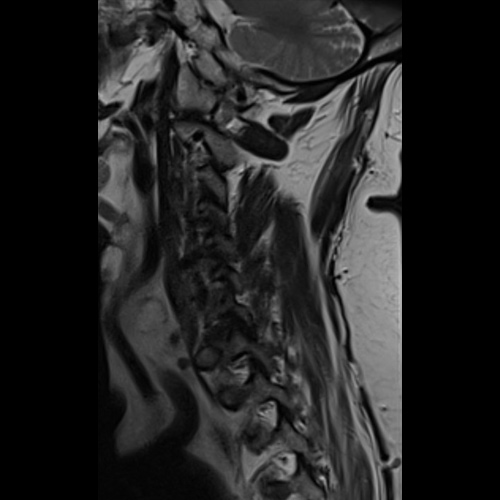

Spinal stenosis (Lumbar) Spinal stenosis (Cervical) Spinal stenosis (Thoracic) Lumbar Disc Herniation Spondylolisthesis Cervical Foraminal Stenosis Vertebroplasty Lumbar Fusion Anterior Cervical Fusion (ACDF) Posterior Cervical Fusion Thoracic Fusion Revision Lumbar Fusion Surgery Facet Joint Cyst Spinal Tumour Minimally Invasive Lumbar Fusion (XLIF) Minimally Invasive Lumbar Fusion (ALIF) Lumbar Fusion (TLIF) Thoraco-lumbar Fusion Lumbar Corpectomy Complex Lumbar Spine Surgery (Spino-pelvic fixation) Complex Cervical Spine Surgery Complex Thoracic Spine Surgery Occipito-cervical Fusion Minimally invasive surgery for thoracic disc herniation Other Related Topics